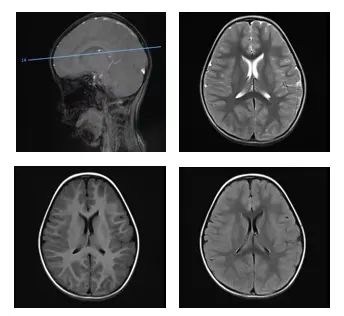

효월은 체액을 보충하고 치료하는 과정에 점차 졸음이 몰려오고 의식이 흐릿해졌으며 두눈을 뒤집고 응시하는 등 증상이 나타나더니 나중에는 혼수상태에 빠졌다.

응급치료를 받은 후 효월은 중환자실 (PICU)로 옮겨졌다. 검사 결과, 효월은 급성 알콜 중독과 심한 대사성 산중독, 대뇌 기능 손상 등 진단을 받았다.

이틀 동안 치료한 후 효월은 드디여 정신을 차렸고 1주일 뒤 신경내과로 옮겨져 재활치료를 계속했다. 최근 재검사에서, 효월은 말이 느린 것 외에는 별다른 문제가 없었다.